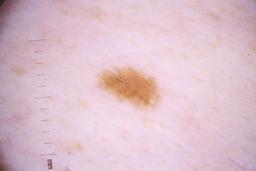

ISIC_4077341

Clinical

| Field | Value |

|---|---|

| acquisition_day | 1 |

| age_approx | 50 |

| anatom_site_1 | Trunk |

| anatom_site_2 | Anterior trunk |

| concomitant_biopsy | False |

| dermoscopic_type | contact non-polarized |

| diagnosis_1 | Benign |

| diagnosis_confirm_type | serial imaging showing no change |

| family_hx_mm | False |

| image_type | dermoscopic |

| lesion_id | IL_9238622 |

| patient_id | IP_1969685 |

| personal_hx_mm | True |

| sex | male |